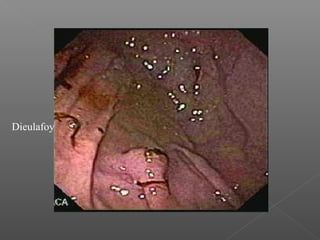

› Erosión de Dieulafoy

Dieulafoy

Argón